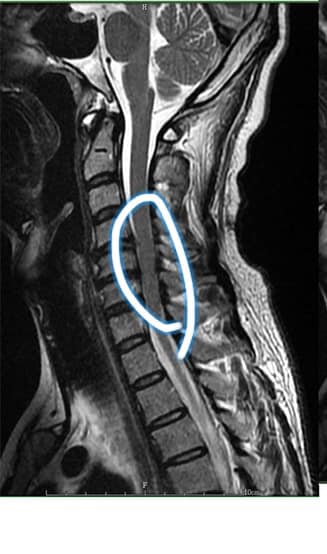

Cervical Spine Treatment Cases 頸椎治療案例 #特殊案例頸椎手術後又再度突出案例 #感謝台中劉大哥熱情見證 #親自手捏醫師娃娃公仔... 2020.11.18 #頸椎病居然會導致手快速萎縮 #脊髓型頸椎病案例 #感謝高雄王大哥熱情見證 #頸椎整合... 2020.11.13 #神經根型頸椎病讓人痛到無法入眠 #感謝新店陳小姐熱情見證 #患者的疼痛日誌讓人感動 ... 2020.11.11 #左邊膏肓長期刺痛案例原來是頸椎病 #之前一直當作肩關節問題處理沒效 #高濃度葡萄糖... 2020.11.03 #腰椎整合醫案逆轉勝 #曾經大痛到無法走路 #坐骨神經痛就是那們痛 #感謝桃園蘆竹張小... 2020.10.29 #特殊案例之味覺錯亂 #原本香甜奶油車輪餅患者覺得酸臭 #按照頸椎病治療五次後突然味... 2020.10.27 頸椎病產生的嚴重交感神經症狀 治療前後比對 2020.10.23 #等待快一年的頸椎受傷醫案追蹤 #頸椎脊髓損傷導致左邊手麻合併下肢無力患者 #前後一... 2020.10.14 #最複雜多變最痛苦難受的頸椎病 #多年的胸悶與心悸伴隨呼吸困難 #交感神經型頸椎病 #... 2020.10.13 #頸椎曲線弧度非常重要 #頸椎弧度有可能逆轉嗎 #短短三個月時間看到效果 #患者超認真... 2020.10.09 #打壘球居然腳不聽使喚跑不起來 #更恐怖的是勉強跑起來還無法剎車 #洗頭往後仰身體背... 2020.10.07 #疼痛三年頸椎病患者親手寫下治療紀錄 #交感神經型頸椎病 #症狀錯綜複雜 2020.10.02 #困擾四年多胸悶手麻頭暈醫案 #一切原因居然是頸椎出問題 #交感神經型頸椎病症狀錯綜... 2020.09.11 #交感神經型頸椎病引起的耳鳴 #耳鳴將近八個月終於得到重大改善 #曾經耳鳴到無法睡覺... 2020.08.22 #感謝板橋蘇先生熱情見證 #神經根型頸椎病卡壓 #曾痛痛到左手無法騎單車撥桿 #麻脹刺... 2020.08.04 ← 上一頁 4 5 6 7 8 下一頁 →